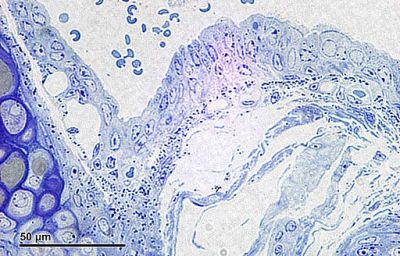

Trachea, mouse - histology slide

Trachea: Mouse trachea cross-section, embedded in Epon. Stain: Toluidine blue. Optical microscopy technique: Bright field. Magnification: 1360x (for picture width 26 cm ~ A4 format).